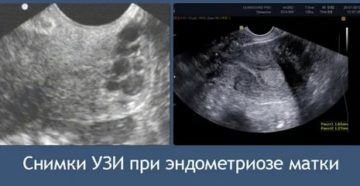

Как эндометриоз отображается на УЗИ? Эндометриоз — это такое заболевание, при котором ткань, которая обычно…